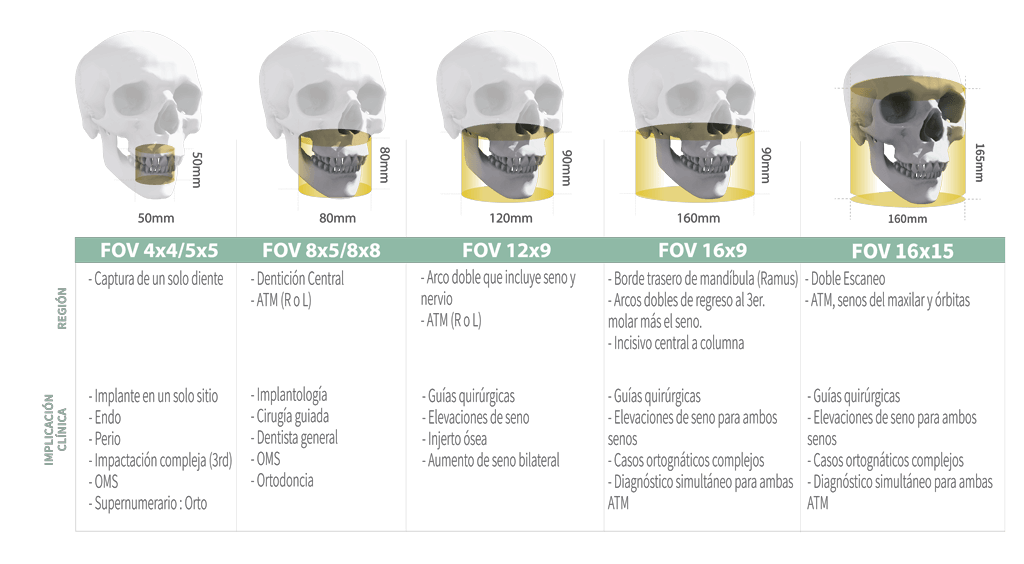

GRAN FOV DE ESCANEO

Green X tiene una amplia gama de campos de visión para que puedas elegir FOV óptimo minimizando la exposición en áreas que no están en la región de interés.

La selección de FOV se adapta a tus necesidades de diagnóstico: 16×15 (opcional), 16×9, 12×9, 8×9, 8×5, 5×5 y 4×4. Estas opciones abarcan toda la región del arco, seno y ATM (izquierda /derecha) y se adapta a la mayoría de los casos de cirugía y cirugía de implantes múltiples.